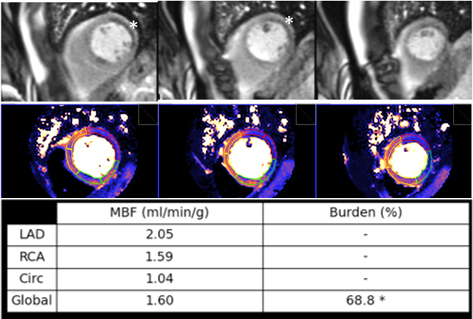

Multivessel disease is a scenario where the diagnostic performance of perfusion

studies visually assessed is particularly challenging. Defects from different

territories are not necessarily homogenous (Figs. 7,8,10), and CMR, although

superior to SPECT, fails to identify visual defects in all territories in up to a

third of patients with three-vessel disease [84]. This figure was shown to be as

low as one-half in a subsequent study where QP was fairly more accurate (87%)

than visual assessment for correctly identifying three-vessel disease when any

coronary territory with

Fig. 35.Ischemic burden in multiple vessel disease as assessed by QP. Stress perfusion (top row) showing a marked defect at the lateral wall (asterisks) while the assessment of the rest of segments is uncertain. Derived from the perfusion mapping (middle row), and assigned to coronary territories, are values of MBF (bottom row) indicating significant inducible ischemia for the territory of the circumflex artery, clear impairment of the RCA, and mostly preserved LAD region, all accounting for a global ischemic burden of 68.8%.